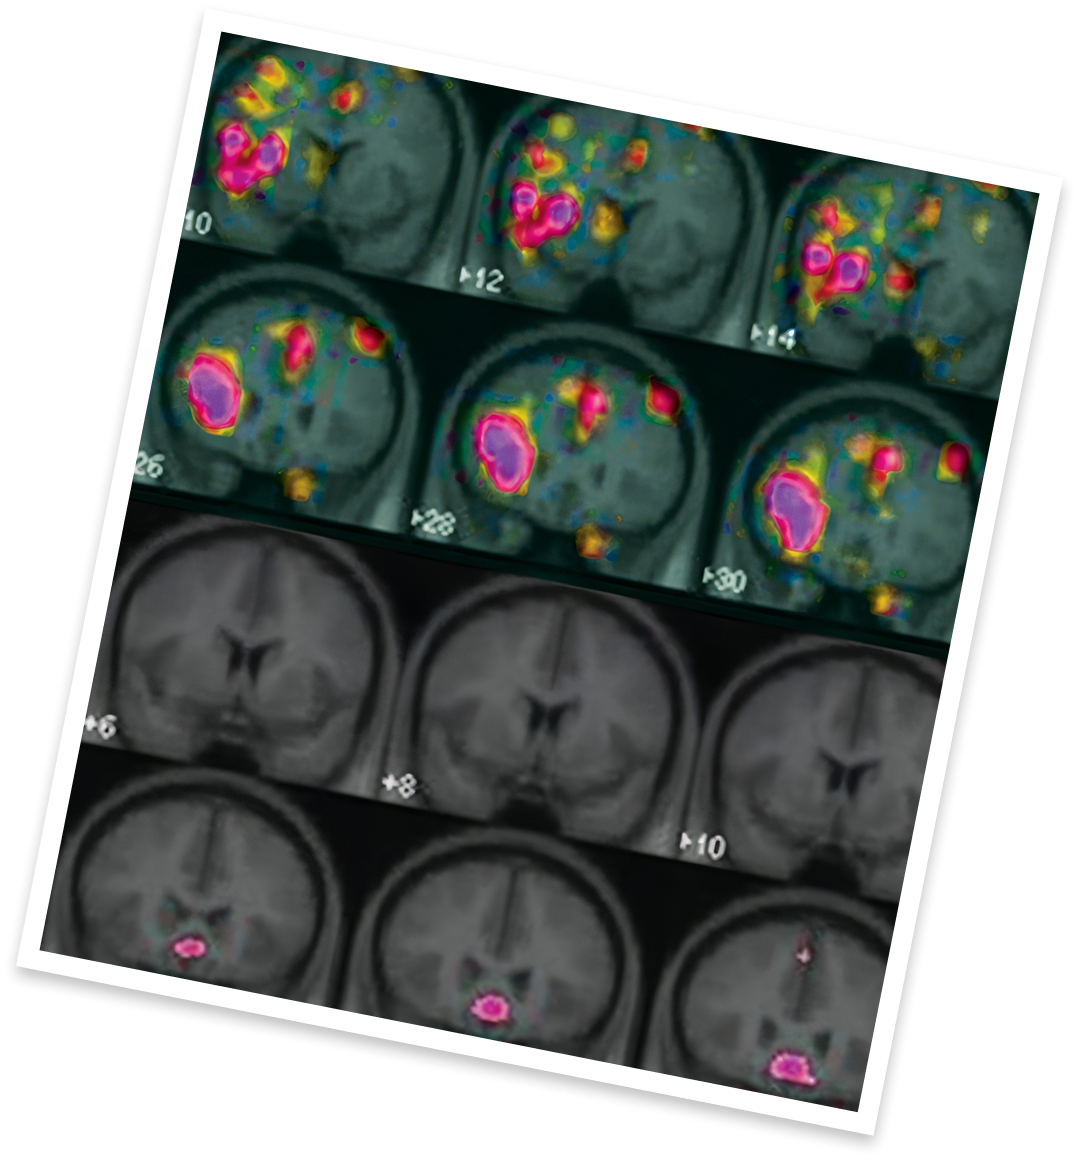

Female fMRI NHSD vs HSDD.

HSDD is believed to be caused by an imbalance of chemicals in the brain. A PET scan study examined 24 women (age 18-47) with and without HSDD by having them watch neutral, low and high erotic movies for 2 minutes while lying with their head in a PET scanner.

Results showed that the women with HSDD had little to no activation in areas of the brain that normally respond to sexual cues. Increased activation was also viewed in the prefrontal cortex, which blocks the progression of desire.10-13

HSDD is believed to be caused by an imbalance of chemicals in the brain. A PET scan study examined 24 women (age 18-47) with and without HSDD by having them watch neutral, low and high erotic movies for 2 minutes while lying with their head in a PET scanner. Results showed that the women with HSDD had little to no activation in areas of the brain that normally respond to sexual cues. Increased activation was also viewed in the prefrontal cortex, which blocks the progression of desire.10-13